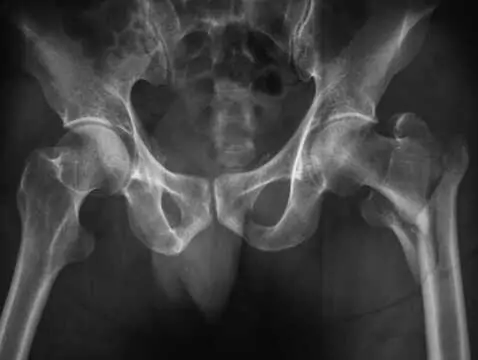

Zwiększona podatność układu kostnego na złamania i zniekształcenia objawiająca się w okresie menopauzy.